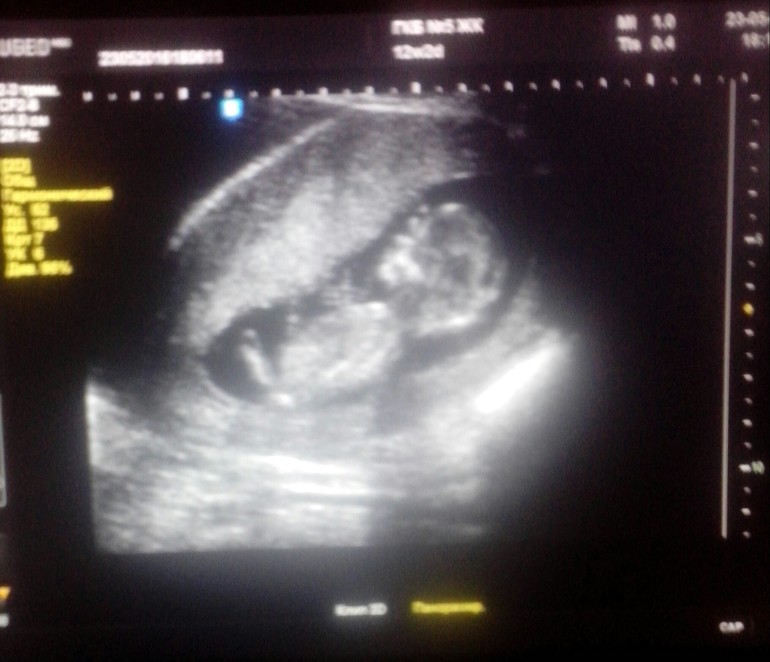

Вчера я его прошла. Срок 12+2 недели. Сейчас вот сижу в очереди на кровь. Все у нас хорошо)) А главное, грыжи нет!!! Как и обещали, втянулась) Крош подрос, есть тонус, точнее пока УЗИ делали появлялся-исчезал. Но с Сашей также было, говорят реакция на волны. А мне кажется, я в туалет хотела. Еще Сашок в машине в это время спала, переживала я вдруг проснется, а меня нет. Но обошлось.

Наши параметры : КТР 61,5 мм (12+4 нед.), ЧСС 176 уд/мин, ТВП 2 мм, БПР 19 мм, дл.бедра 7,5 мм, локализация хориона передняя стенка (большой живот будет???). Еще сказали, что похоже на девочку.